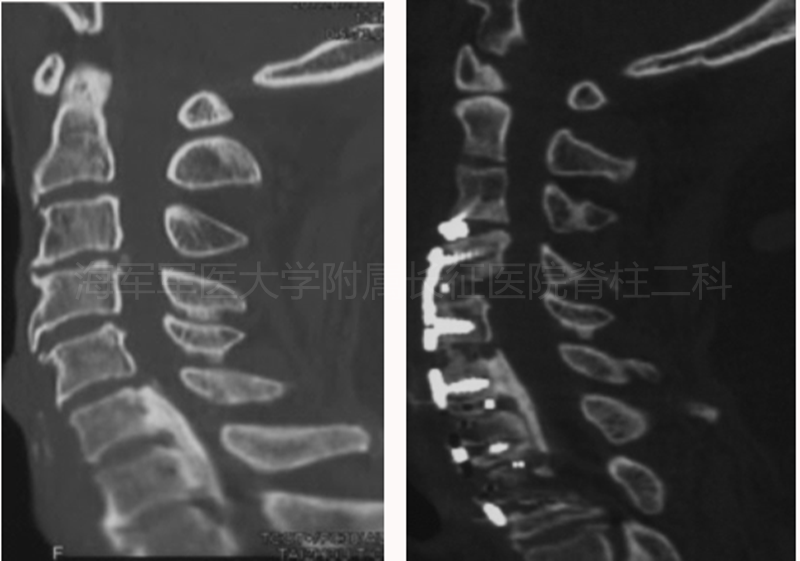

术前术后矢状位MRI对比

术前术后水平位MRI对比